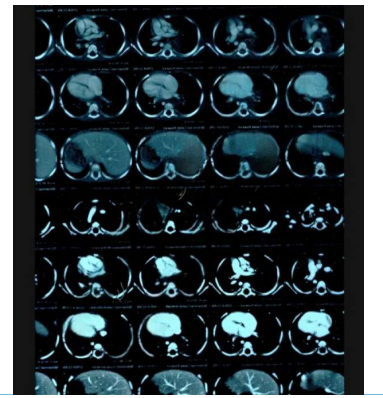

A contrast-enhanced Computer Tomography Scan of the chest showed: a large mass filling the posterior mediastinum in it's upper and middle parts, aligned with the visceral side of the right upper lobe.

MRI showed: a mass in the posterior mediastinum surrounding the tracheal branch and reaches the diaphragm, surrounding the Azygos vein, superior vena cava, aorta, major vessels and esophagus, measuring (11*5*7) cm. and foci osteolysis in the 9,11,12 thoracic vertebrae.

With an annual periodic review, for blood tests and a chest CT scan that showed a decrease in the size of the lymphangioma.

With an annual periodic review, for blood tests and a chest CT scan that showed a decrease in the size of the lymphangioma